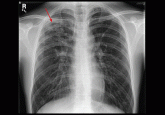

ArticleRule out pulmonary tuberculosis: Clinical and radiographic clues for the internistAuthor:Catherine Anne Curley, MDPublish date: January 1, 2015A foreign-born college student presents with fatigue, weight loss, and a cough. Could it be tuberculosis?Read More